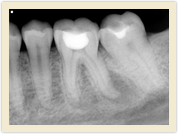

![]() |

| Before Photo | After Photo |